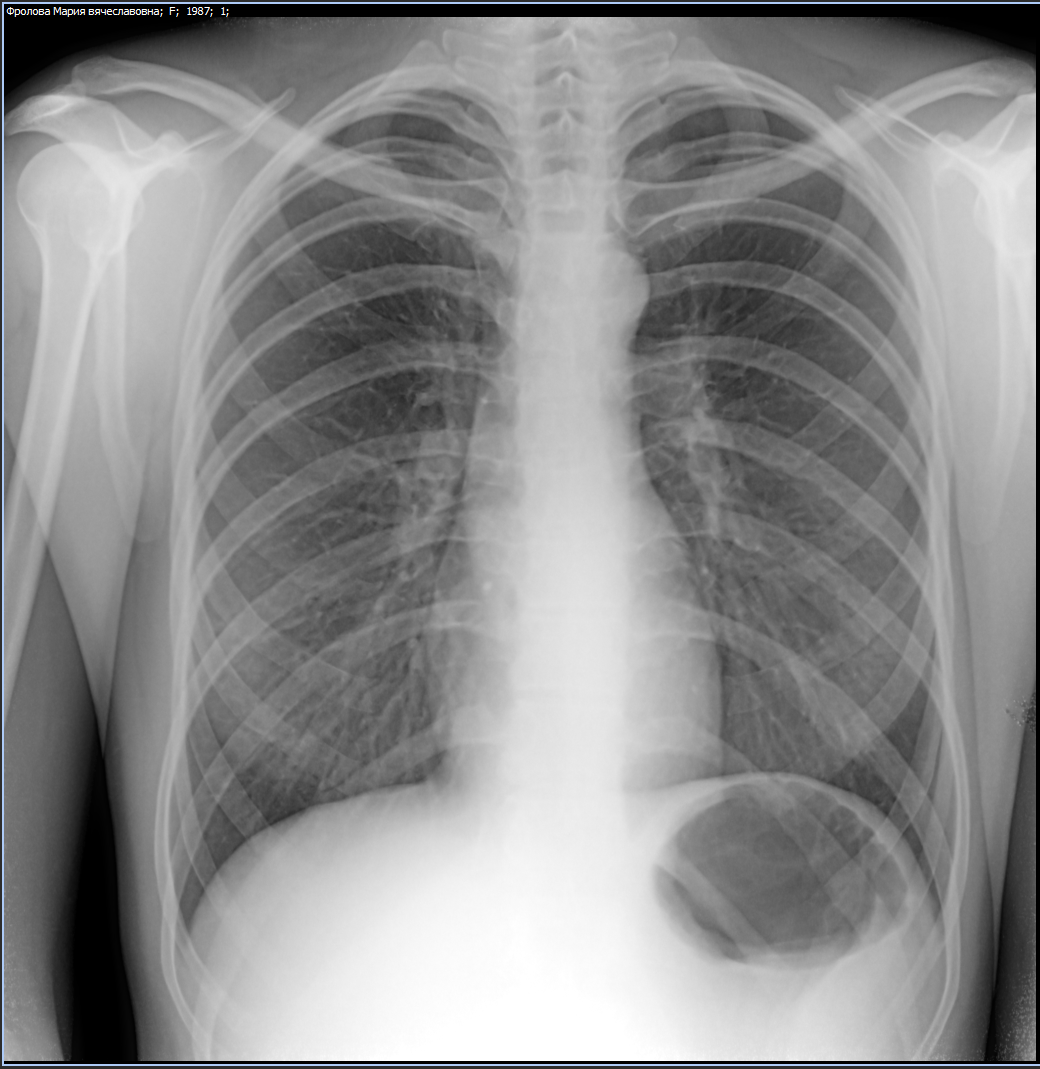

Снимок грудной клетки здорового ребенка: примеры и диагностика

Раздел: Мудрость в объективе